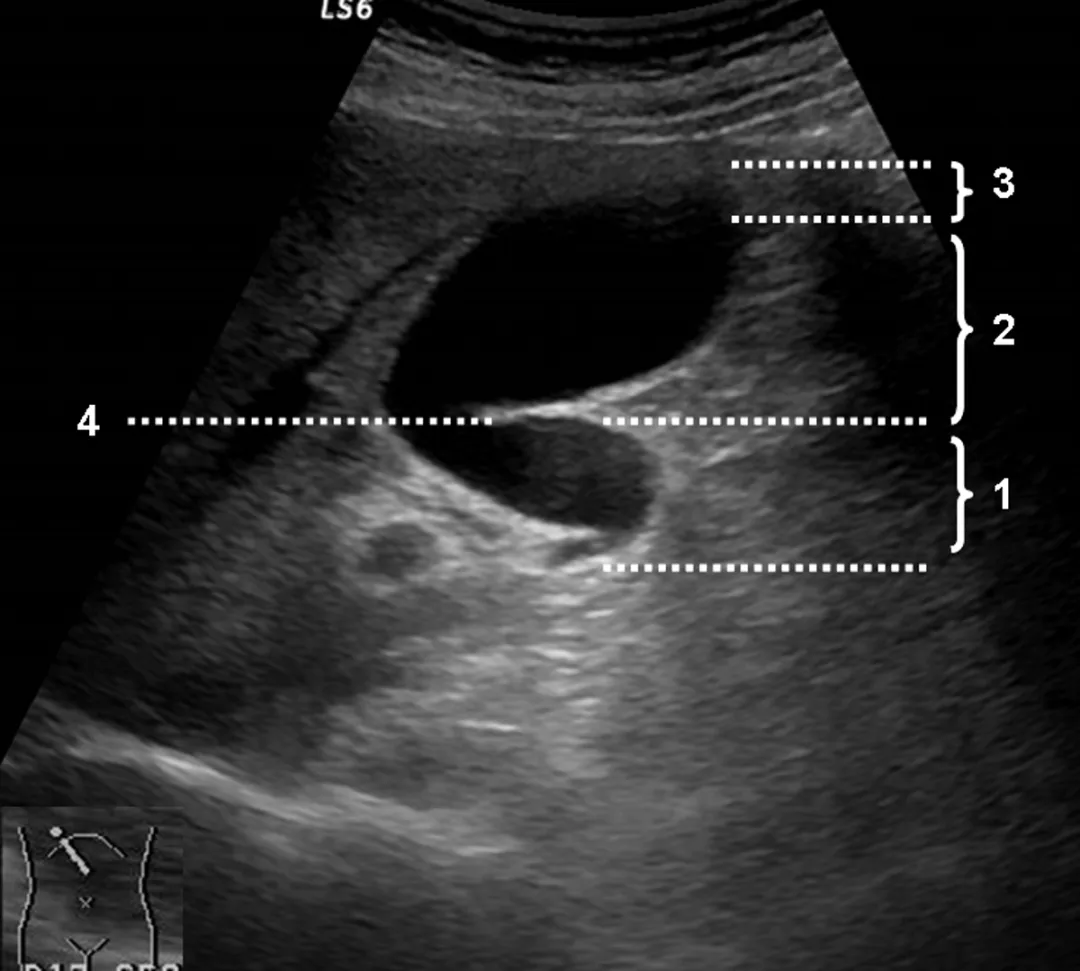

正常超声表现

胆囊位于胆囊窝内

纵切面呈梨形

横切面呈圆形或椭圆形

长径50~80mm, 横径30~40mm,胆囊壁厚度不超过3mm,多数小于2mm。

1:胆囊颈;2:胆囊体;3:胆囊底;4:胆囊皱褶

探头置于右肋缘下,大致与肋弓垂直,左右侧动探头,显示较完整的胆囊长轴断面,测量胆囊的长径和横径。

正常值:长径<10cm,横径<3.5cm